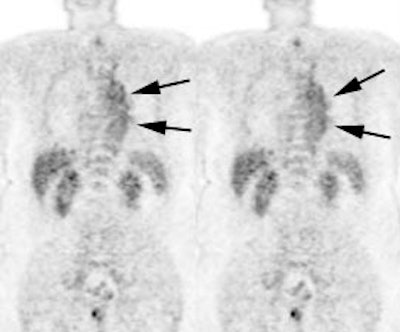

Vascular graft activity: The patient below had a prior graft repair of an ascending aortic aneurysm. Tracer uptake can be seen in the ascending aortic graft (black arrows). The patient also has a left upper lobe lung cancer (red arrows). |

|